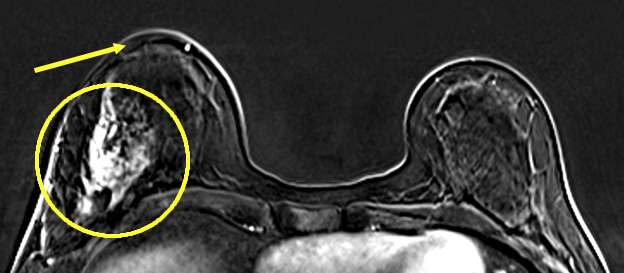

MRI: Provides detailed images demonstrating the extent of skin involvement and characteristics of a potential underlying malignancy.

- MRI: Provides generally provides excellent visualization of the nipple and the breast tissue in the subareolar area to evaluate for potential abnormal pathology and extension into the duct system.

- MRI: Helpful in assessing the extent of skin involvement and distinguishing between benign and malignant causes of skin thickening and assessing for underlying malignancies.